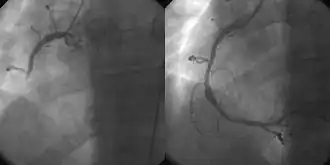

Angiografie der rechten Herzkranzarterie (RCA) bei akutem Hinterwandinfarkt, links: RCA verschlossen, rechts: RCA nach Ballondilatation offen

Vordringliches Therapieziel beim ST-Hebungsinfarkt ist die möglichst rasche Eröffnung des betroffenen und in dieser Situation meist verschlossenen Herzkranzgefäßes. Diese Wiederherstellung der Durchblutung im Infarktgebiet wird Reperfusionstherapie genannt. Je früher diese erfolgt, umso besser kann eine Infarktausdehnung verhindert werden („time is muscle“). Gelingt es, die Reperfusionstherapie bereits in der ersten Stunde nach Infarkteintritt anzuwenden, so können viele dieser Infarkte sogar verhindert werden.